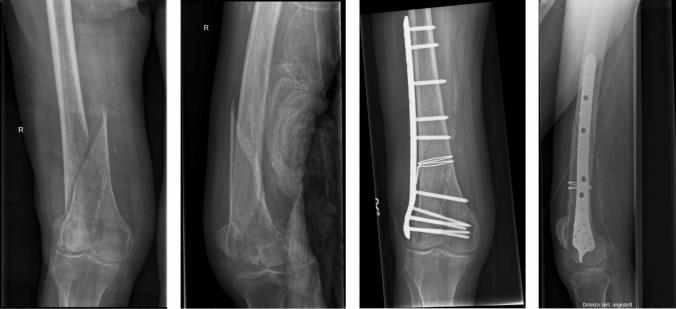

More than a reposition tool: additional wire cerclage leads to increased load to failure in plate osteosynthesis for supracondylar femoral shaft fractures.

Surgical treatment of supracondylar femoral fractures can be challenging. An additional wire cerclage is a suggested way to facilitate fracture reduction prior to plate osteosynthesis. Denudation to the periosteum remains a problematic disadvantage of this procedure. This study analyzed the effect of an additional wire cerclage on the load to failure in plate osteosynthesis of oblique supracondylar femoral shaft fractures.

On eight pairs of non-osteoporotic human femora (mean age 74 years; range 57-95 years), an unstable AO/OTA 32-A2.3 fracture was established. All specimens were treated with a polyaxially locking plate. One femur of each pair was randomly selected to receive an additional fracture fixation with a wire cerclage. A servohydraulic testing machine was used to perform an incremental cyclic axial load with a load to the failure mode.

Specimens stabilized with solely plate osteosynthesis failed at a mean load of 2450 N (95% CI: 1996-2904 N). In the group with an additional wire cerclage, load to failure was at a mean of 3100 N (95% CI: 2662-3538 N) (p = 0.018). Compression deformation with shearing of the condyle region through cutting of screws out of the condylar bone was the most common reason for failure in both groups of specimens. Whereas axial stiffness was comparable between both groups (p = 0.208), plastic deformation of the osteosynthesis constructs differed significantly (p = 0.035).

An additional wire cerclage significantly increased the load to failure. Therefore, an additional cerclage represents more than just a repositioning aid. With appropriate fracture morphology, a cerclage can significantly improve the strength of the osteosynthesis.